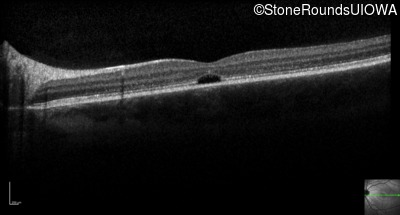

Optical Coherence Tomography - Right - 20/160 +2

Exemplar / OCT Stack

OCT Stack